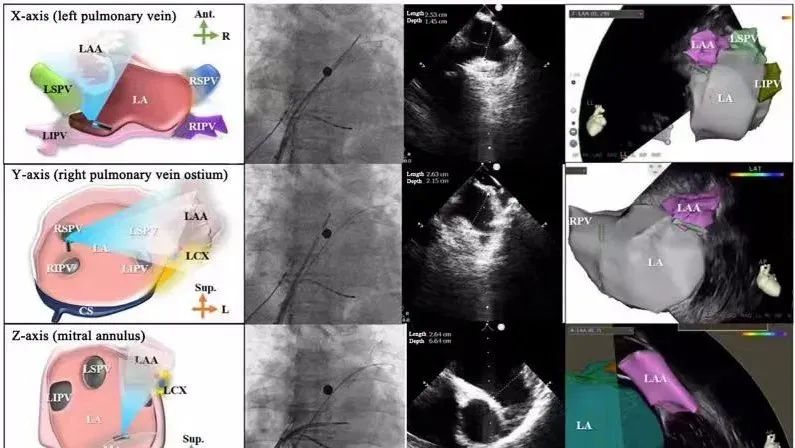

一種與心導(dǎo)管檢查相結(jié)合的超聲心動圖診斷新興技術(shù),通過將超聲探頭置于心腔內(nèi)部,發(fā)射并接收超聲信號,來精確獲取心臟解剖結(jié)構(gòu)、心臟血流動力學(xué)等信息的實時成像。與其他影像技術(shù)相比,ICE技術(shù)具有操作簡單、無輻射、安全性高、手術(shù)效率高、實用等優(yōu)勢,ICE在很大程度上有望取代經(jīng)食道超聲心動圖(TEE),成為電生理和結(jié)構(gòu)性心臟病領(lǐng)域的理想成像方式。

心腔內(nèi)超聲(ICE)技術(shù)壁壘極高,國內(nèi)主要廠商核心部件仍舊為進口,集成了超聲和圖像處理最前端技術(shù),包括超聲探頭、線纜、軟件成像算法等,是當(dāng)前內(nèi)窺超聲方向最具挑戰(zhàn)的領(lǐng)域。ICE的應(yīng)用經(jīng)歷了2D平面成像、3D三維立體成像、以及4D的實時三維立體成像階段。